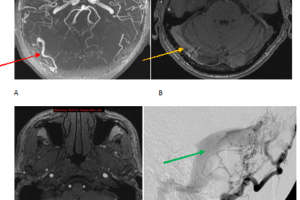

Dural Arterio-venous Fistula

Dural arterio-venous fistulas are a rare but important category of intracranial vascular abnormalities. They are characterized by arterio-venous shunting within the dura and are most commonly a sequelae of trauma. The hypothesized... Read more »